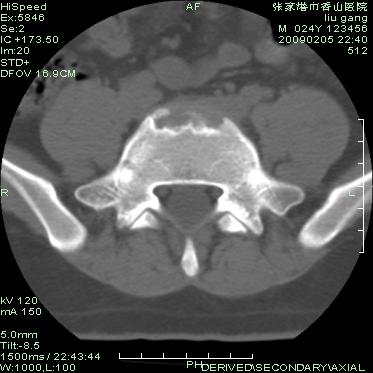

以下是引用随光逐影在2009-3-11 14:43:00的发言:[br]平片:l3、4、5及s1前上缘见类似“切角征”。[br]ct扫描:腰椎多个节段椎间盘向椎体内(椎体前部)突出。